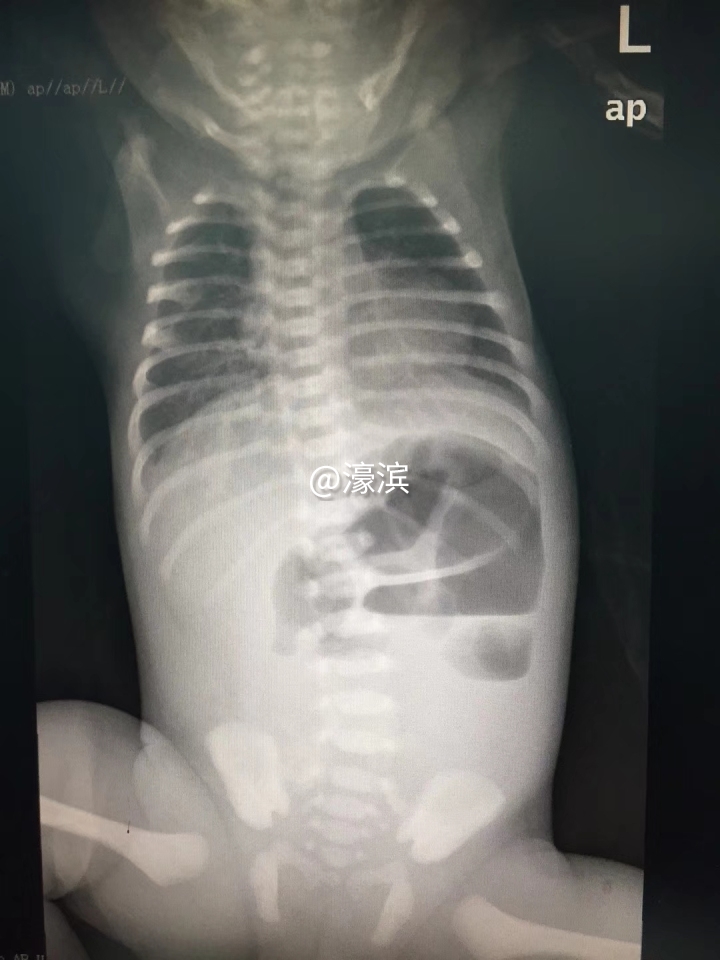

“当时看到孩子的症状后,我根据临床经验判断,这很可能是消化道发育畸形所致。”该院儿外科主任医师张友波介绍,X线检查证实了他的判断:肠管扩张不通,消化道发育异常,属于先天性肠闭锁。

“正常人的肠管是畅通无阻的,可以蠕动和排便,而先天性肠闭锁的患儿肠管中间闭锁,从而导致腹胀、呕吐、无法正常排便。”张友波介绍,聪聪肠管出现闭锁的部位位于小肠的上半段,这个位置叫做“空肠”,因此,患儿属于“先天性空肠闭锁”,且为病情比较复杂严重的多发性闭锁(IV型)。而手术则需要将病变闭锁的肠管切除,同时将正常的肠管两端接通,使其恢复肠道的连续性,并有正常蠕动和排便。

4月23日,张友波团队紧急为出生仅48小时的聪聪实施了全麻支持下的“腹腔镜辅助肠切除吻合术”,整个手术耗时3个小时。对出生仅48小时的一个小生命实施外科手术,其难度可想而知。“患儿腹腔内肠粘连严重,加上空肠闭锁近端严重扩张,肠管直径5cm,闭锁远端肠管纤细,发育不良,直径仅为0.3 cm,两端肠管直径相差太大,吻合困难,进一步增加了手术难度。”在整个手术过程中,儿外科、麻醉科、手术室、新生儿科的多名医护人员通力合作,在切除20 cm病变肠管后,采取肠端侧吻合的方式,为聪聪成功接通肠管,恢复了肠管的连续性。